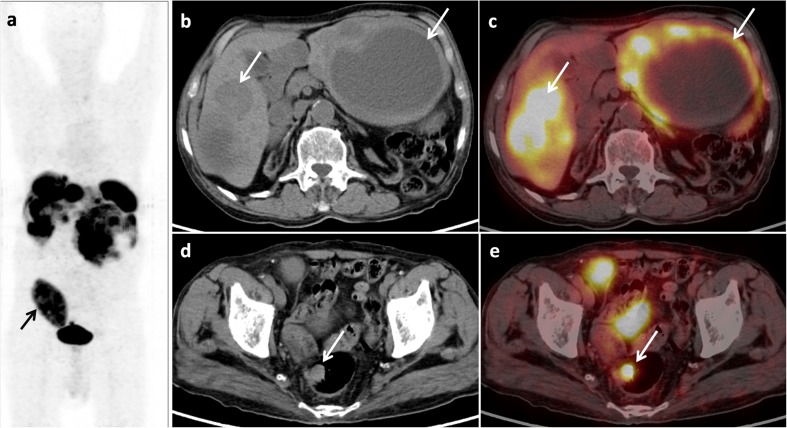

Fig. 1.

Maximum intensity projection 18F-FDG PET image (a), trans-axial CT (b) and PET-CT (c) images revealing multiple hypodense lesions in both lobes of the liver with increased 18F-FDG uptake (SUVmax = 2.9) on the periphery of the lesions (b, c; arrow). Also a nodular FDG-avid lesion was noted in the rectum (SUVmax = 5.4) (d, e; arrow), suggestive of a primary. The transplanted kidney is visualised in the right iliac fossa (a; arrow)